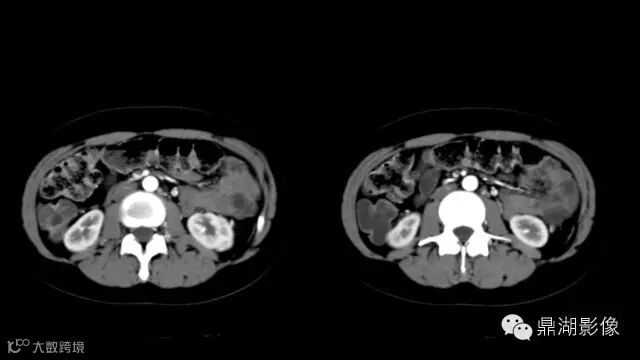

do you know comb sign?

The comb sign refers to the hypervascular appearance of the mesentery in active Crohn disease.

It is the comb sign the most specific sign for crohn's disease.